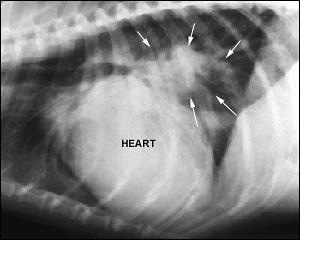

高齢犬・老犬の重大な心臓病として一番にあげられるのが、夏場に発生する蚊が媒介する寄生虫の病気【フィラリア】でしょう。

フィラリアと呼ばれる寄生虫が心臓内部に寄生しておこり、かなり重大な病気のひとつです。蚊が媒介する病気で、数年経って徐々に症状がでてきます。はじめはときどき咳がでる程度ですが、慢性化すると咳の度合いも激しくなり、咳の時間も長くなります。慢性化してしまうと治療を施しても、肝臓や腎臓などに異常をきたして、死亡してしまう場合も多い病気です。しかし、獣医学の進歩により経口投与する錠剤や散剤で充分に予防することができます。

小型犬の老齢犬に多いのが僧帽弁閉鎖不全でしょう。心臓の弁がゆるんでしまい完全に閉じないために、肺水腫などになりやすくなる病気です。初期症状はやはり空咳です。その後症状が重くなると貧血をおこし唇や舌が紫色に変色したり、発作を起こして倒れることもあります。生命に関わる大きな病気ですので気になるなら早めに獣医師に相談しましょう。